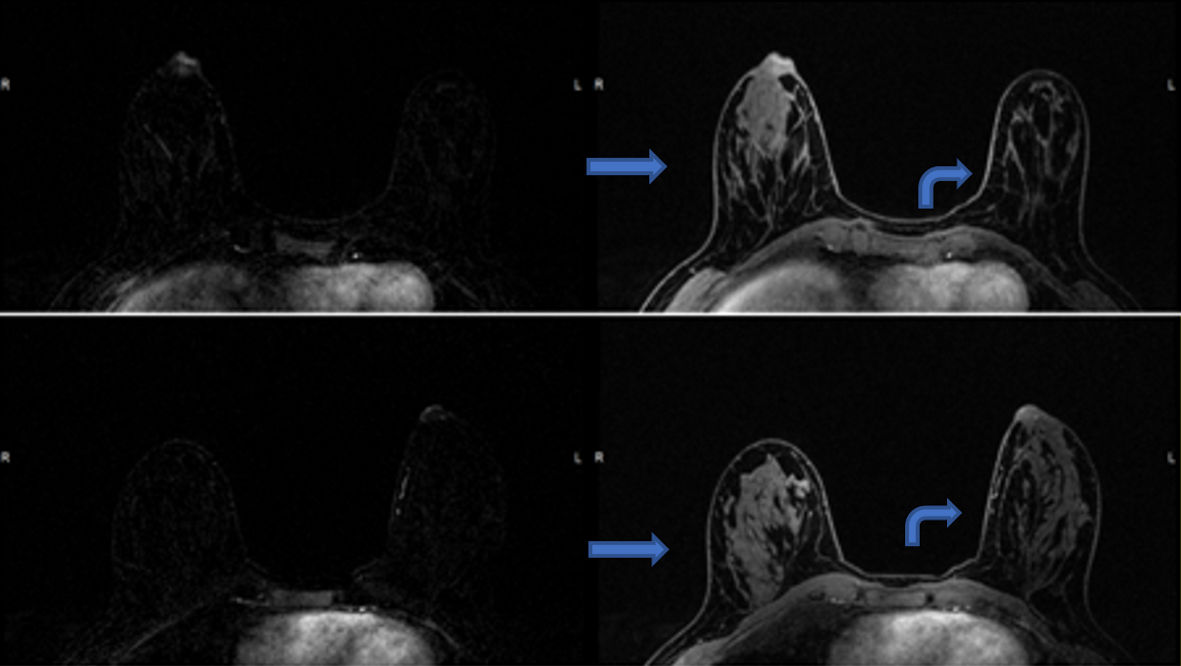

Mammography and targeted ultrasound were unremarkable (Fig. 2a, b). Breast magnetic resonance imaging (MRI) showed asymmetric enhancement of the right nipple (Fig. 3). Nipple excision vs. fine needle aspiration vs. incisional nipple biopsy were reviewed with the patient. After almost 2 years of watchful waiting and expectant management patient with ongoing complaints of nipple pain, she elected for excisional biopsy of her right nipple. Preoperatively, she met with plastic surgery to discuss delayed reconstruction.

![]() Click for large image | Figure 3. Post-contrast T1-weighted fat-suppressed axial MRI images, with subtractions on the left, show asymmetric enhancement of the right nipple (arrows) compared to the left (curved arrows). MRI: magnetic resonance imaging. |

Mammogram findings ranged from normal, to nonspecific, to variably sized calcifications or asymmetry at the nipple-areolar complex or subareolar region. Ultrasound often confirmed the mammographic findings and noted irregularly outlined nodules in the subareolar region of the nipple. One study reported an irregular mass with enhancement on contrast computed tomography (CT), suspicious for malignancy [10]. Only one report noted MRI findings, an irregular mass in the subareolar region of the nipple [11]. Our patient’s breast MRI, related to the symptomatic nipple, noted asymmetric enhancement of the right nipple. This review reveals that imaging of SyT cannot distinguish it from other neoplasms and cannot be trusted to distinguish SyT from carcinoma of the breast.